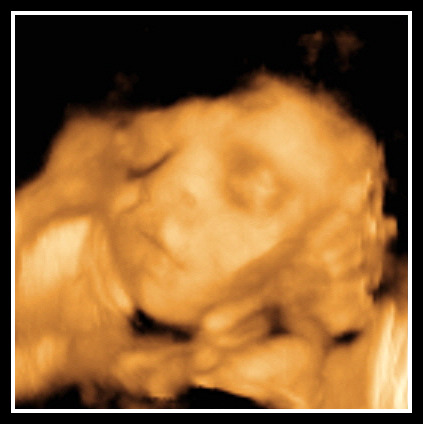

A Miracle Within

I couldn’t resist having a 3D/4D ultrasound even though they are pretty pricey. I noticed when we were buying our furniture that we would get 30% off at A Miracle Within Ultrasound if we brought our receipt totaling more than $50 from USA Baby…we certainly met that requirement! So I scheduled the appointment for the Platinum package. We were the last appointment of the day which was good since BB didn’t seem to want to cooperate…but isn’t that how it usually goes. The tech was so sweet and excited we had decided to keep the gender a secret. She explained how the technology worked and applied the warm goo and there was little Baby Bright. It was amazing to finally get to see our baby’s face. And I always feel better after an ultrasound…it’s really still in there and looks good! We watched as BB moved its face and hands back and forth. And then came the foot! We were battling against all odds to get a clear picture of the face. Both hands, the left foot AND a loop of the cord was around the face practically the whole time. The tech was bound and determined! She poked and prodded and shook and pushed on my belly to get that silly foot to move. She turned me to the side and then to my back again. We got quite a few really good shots but they took some coercing to get! I think BB looks a lot like daddy which I am very happy about…he’s so cute ;). I was really hoping for the Bright nose and I think we’ve got it! It was so strange to see the eyes blink and the baby yawn. You just think its eyes and mouth are closed and it’s always sleeping but it’s not (and I should know that anyway for all the pummeling I’m getting from the inside out!). At one point BB seemed to be scowling as I’m sure the poking and prodding wasn’t too fun in its opinion either! The appointment was only supposed to last 30 minutes but since we were the last appointment of the day and BB was being very uncooperative, the tech let us go over. At the very end, she made her way down (well, up since baby’s head is down…yay). We turned away so the gender could be on our video. She also took a picture to mail to us after the baby is born. She either wrote “It’s a Boy” or “It’s a Girl” on the photo. I can’t wait to get it…how fun. She was so funny…she kept saying don’t look, okay really don’t look. Of course, no surprise here, BB was sitting on its right leg so it took her a minute to get the baby to move a little so she could get a good shot. So now, the tech and God are the only two that know the gender of this baby! We have the video in our TV cabinet and could find out the gender at any time if we wanted but don't worry, we won't watch it until we get home from the hospital. We’ve made it this far but I have to say, some days are hard and I just want to know. I’ve had a few people say they will watch it for me even…they are not allowed over to my house now! So enjoy the pictures of BB…can’t wait to see your face and see if you really have daddy’s nose.

![]() |

| what a sweet little face |

| blowing kisses |

| you can see the bones in the hand...amazing |

| freddie munster? :) the black part isn't hair btw |

| yaaaaawn! |

| flex that muscle! |

| peace out ya'll...see you soon! |